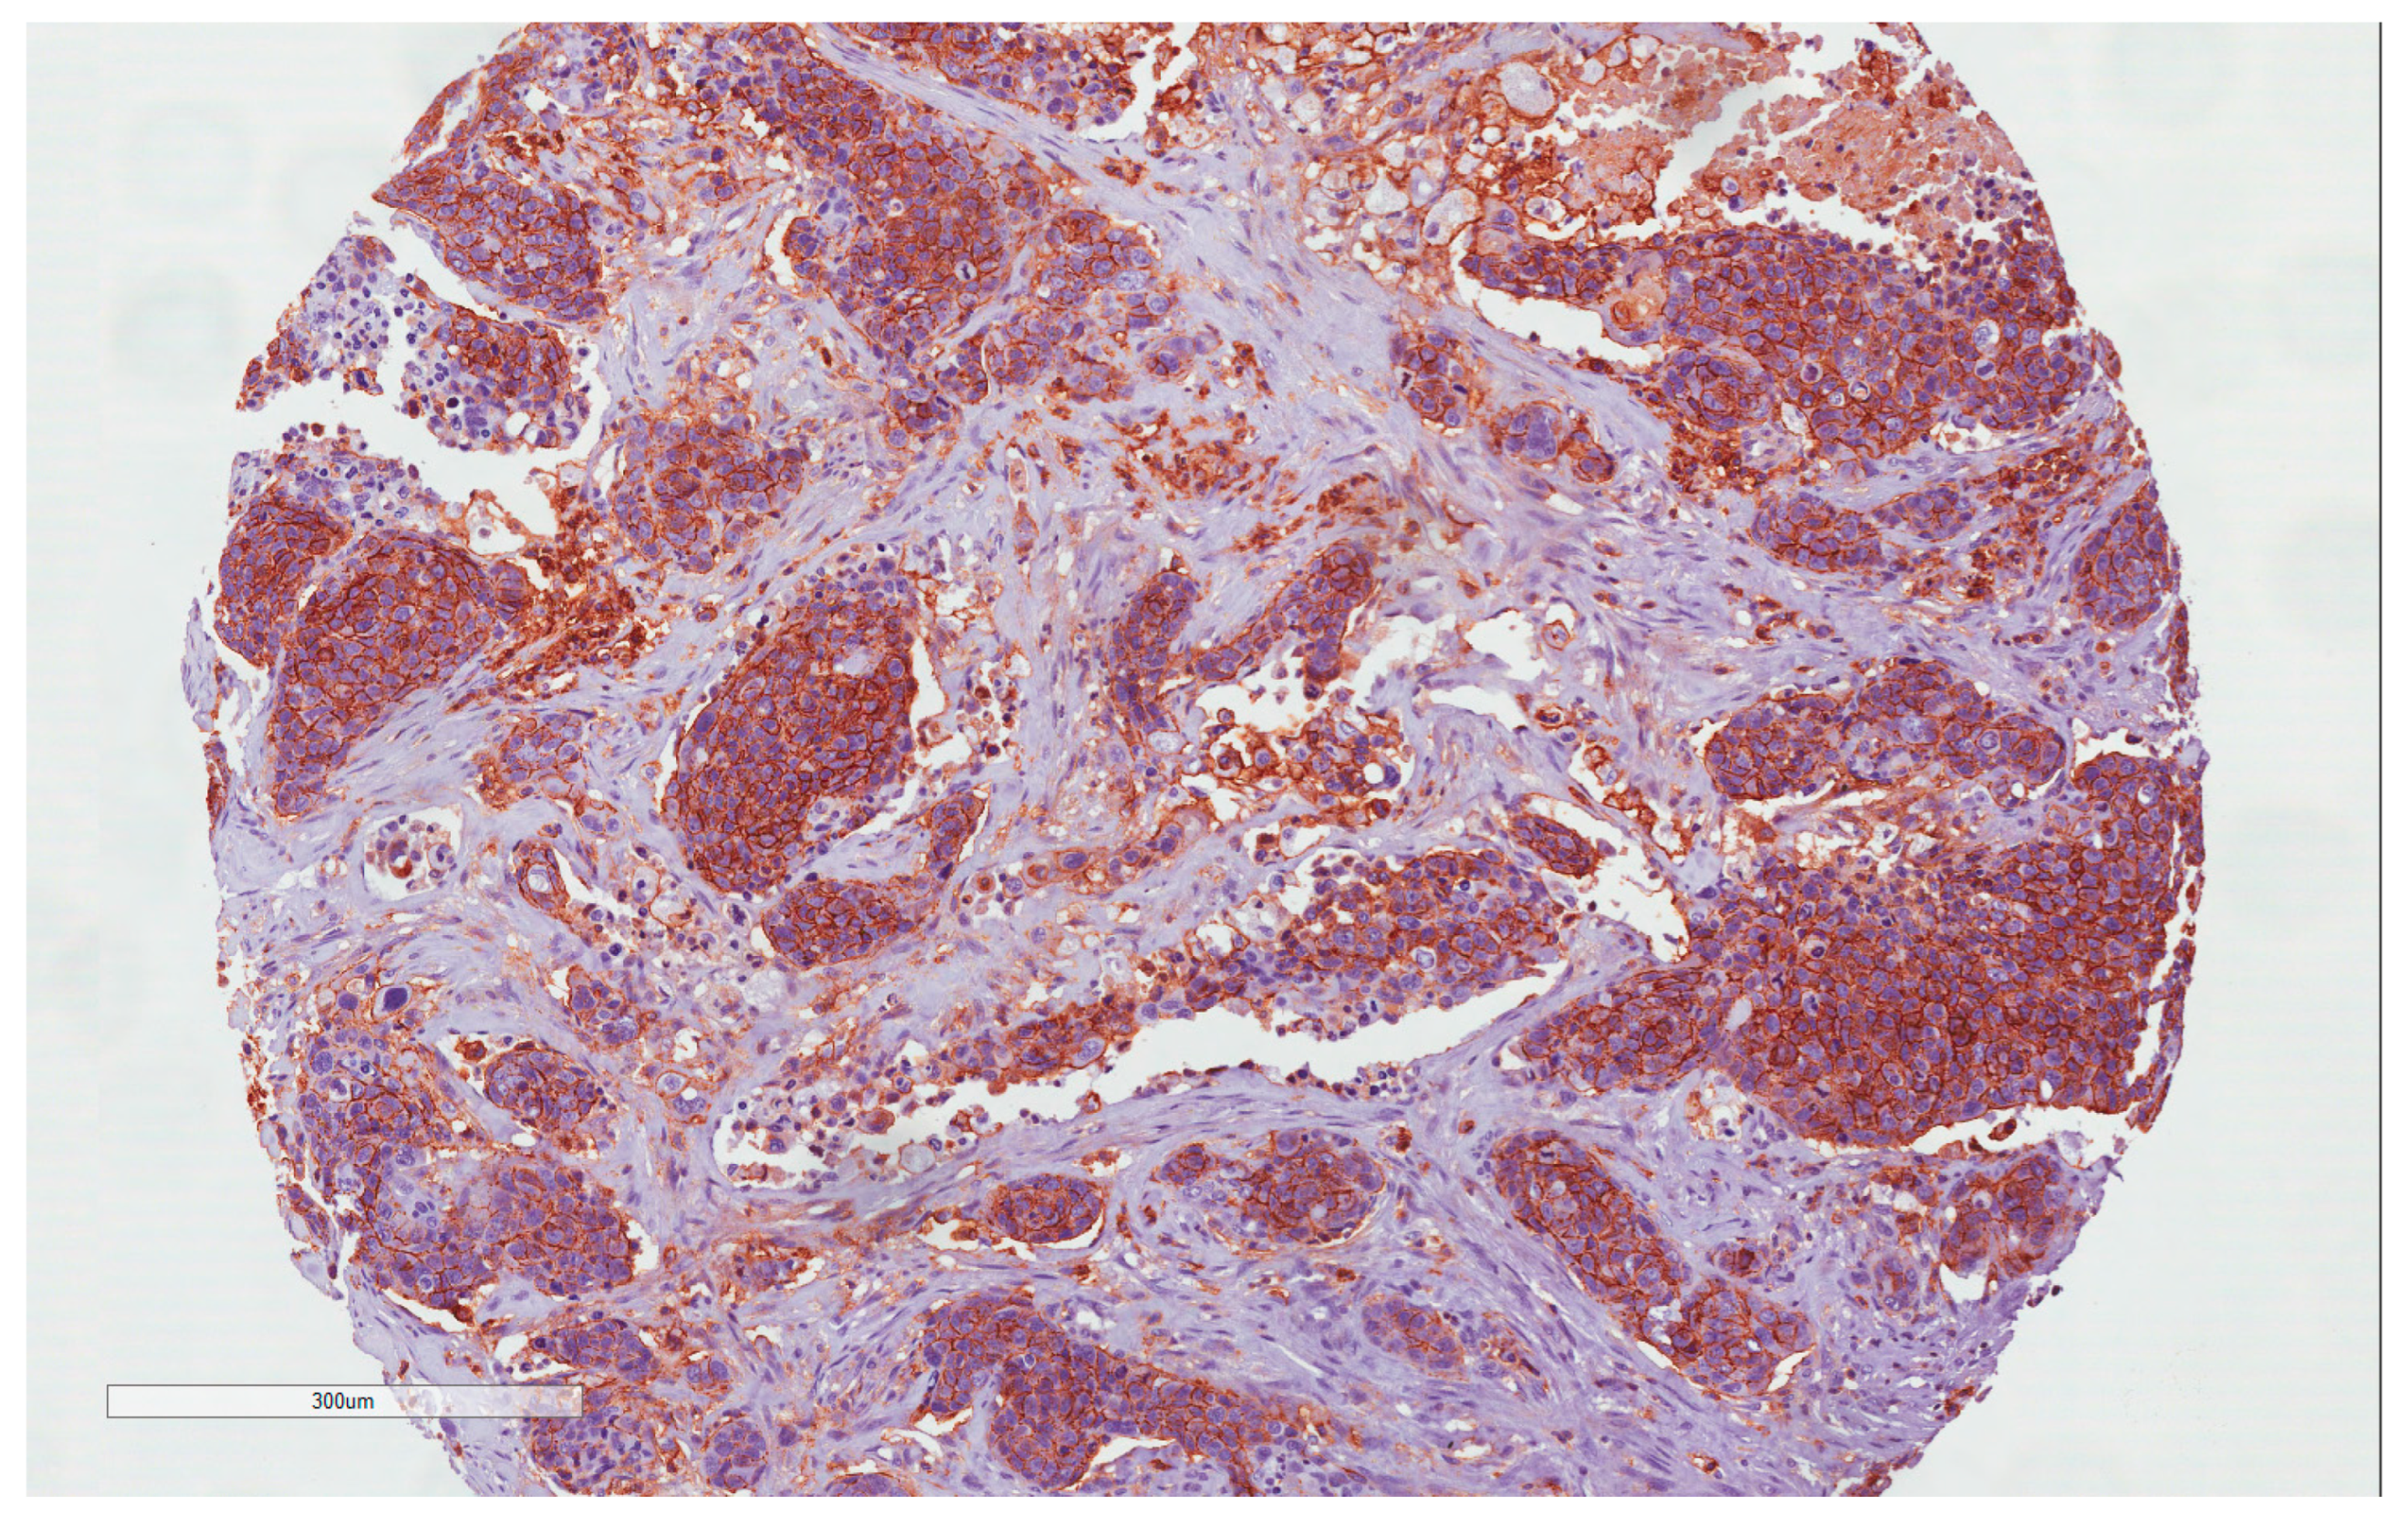

4.2. CD44 Expression

4.3. PDL1 Expression

4.4. ATG7 Expression